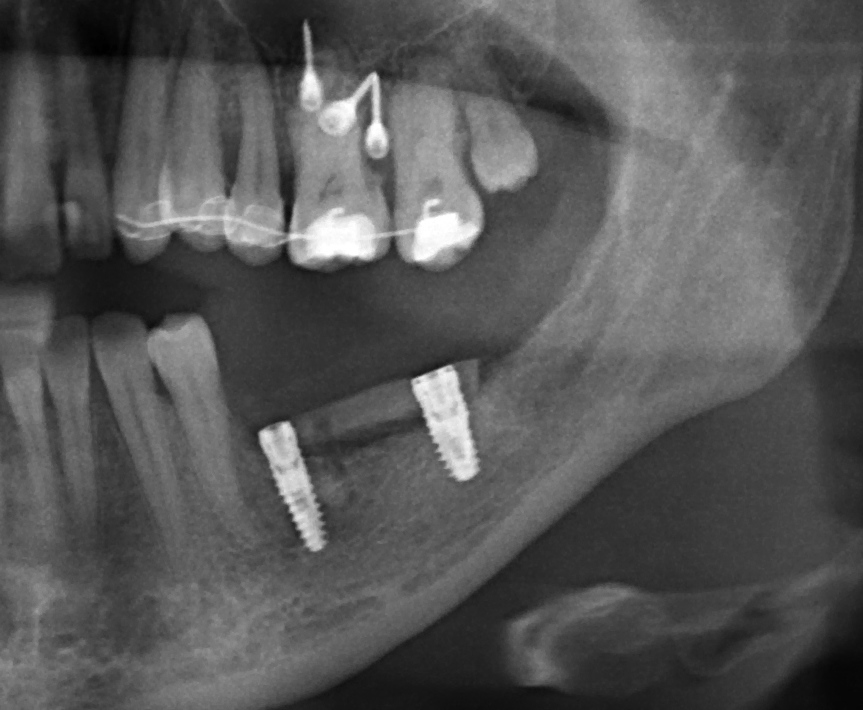

Снимок после проведенной имплантации:

после имплантации 2

Винты, фиксировавшие блок, удалены. Имплантаты позиционированы по разметке ортопеда, исходя из планируемой ортопедической конструкции.

Многих пациентов также интересует, как заживает тот участок челюсти, с которого был взят костный блок для пересадки. На снимке выше очень хорошо видно, что через три месяца костная ткань там почти полностью восстановилась — область забора блока еле видна.